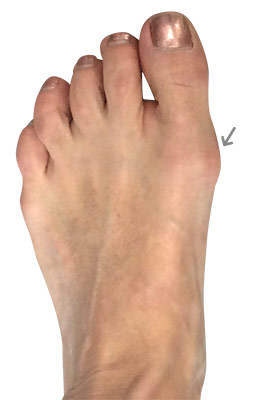

After

Minimally Invasive Bunion Surgery after

Minimally Invasive Bunion Surgery featuring the miniBunon™ System and Tailors Bunionectomy

Melissa is a 32-year-old businesswoman who could not be off her foot post-surgery, yet she had a severely painful bunion. We performed our miniBunon™ System (our trademarked minimally invasive bunion surgery) and had a dramatic correction with no downtime. Melissa continued to work after her bunion surgery and was back in shoes and full activity at 5 weeks. Melissa could not believe the results of her Bunionectomy resulting in no bony bump, no scar and amazing motion. “After” picture taken immediately following surgery. Note the bunion and bunionette (Tailor’s bunion) in the before picture.